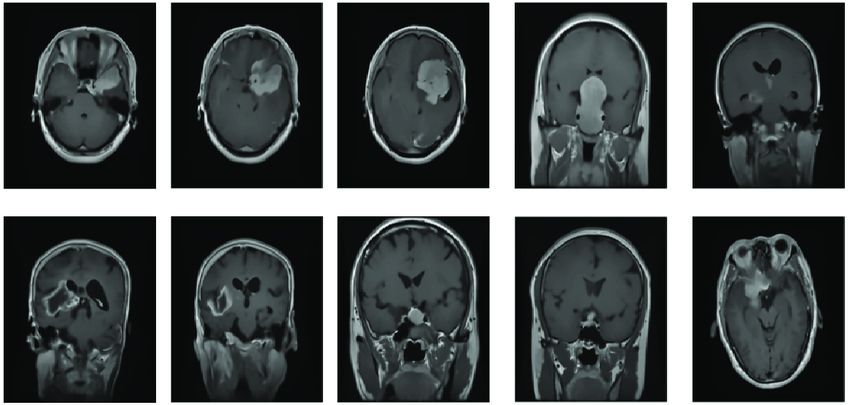

- Their platform, ImagiXAI, supports early disease detection, surgical planning, and AI-generated cranial implants.

Easiofy's flagship platform, ImagiXAI, embodies their mission to "ease and amplify" healthcare delivery. It offers a robust suite of features, including:

- Early detection from X-rays, MRIs, and CT scans

- 3D visualisation tools for surgical planning

- Automated cranial implant design